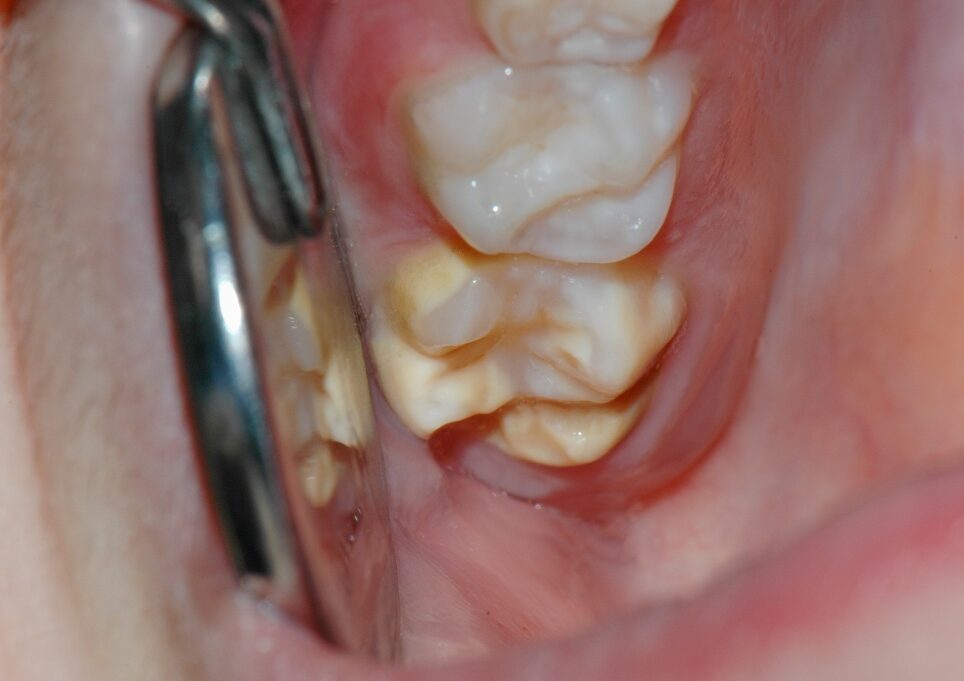

Le sigillature dei molari permanenti

La SIGILLATURA dei denti è una procedura dentistica raccomandata per prevenire la formazione di carie, da eseguire non appena i denti da latte lasciano il posto a quelli permanenti. La sigillatura dei denti è consigliata, in particolare, per prevenire lo sviluppo di processi cariogeni nei molari permanenti. Difatti, questi denti sono più esposti al rischio…